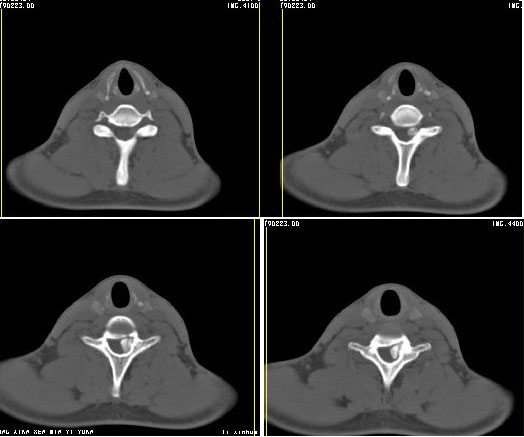

强化

标题: 考虑骨软骨瘤可能性大

椎管内骨性肿块,与第7颈椎左下关节突关系密切,向椎管内生长,第7颈椎椎体左后缘受压变形,边缘可见硬化边,与肿块间间隙清晰。mri扫描肿块内可见骨髓信号,考虑骨软骨瘤可能性大。

虽然没有看到基底 仍考虑骨软骨瘤